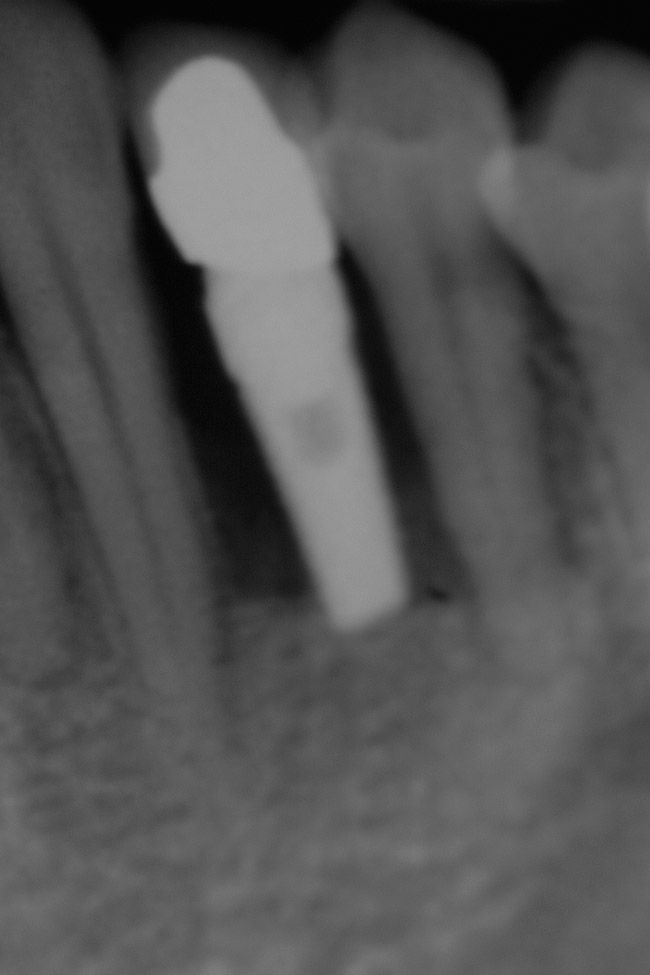

Figure 21  Radiograph of implant in position at the time of surgery of tooth No. 23.

Figure 21

Figure 23  Postoperative radiograph of zirconia abutment.

Figure 23